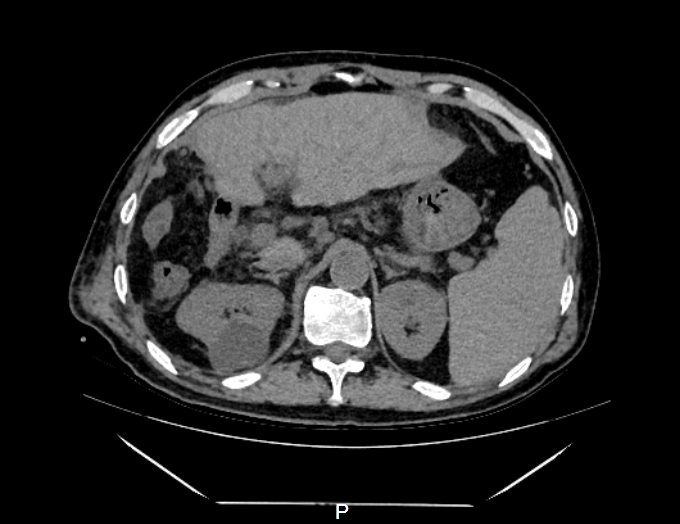

肿瘤体积超过半个肝 71岁的刘先生最近背部酸痛明显,活动受限,行走困难,就连晚上睡觉也只能趴着睡,但凡一扯到背部的肌肉,那种剧烈的疼痛让他直冒冷汗,连续贴了一个多月的膏药也无法有效缓解。 放心不下的他来到了浙江省人民医院越城院区就诊,医生为他做了胸片CT平扫后,发现他的肝脏部位隐隐约约有一个很大的肿块,建议做进一步的检查。 突如其来的噩耗让刘先生担忧不已,多方打听下,他慕名来到了肝胆胰外科、微创外科主任助理尚敏杰副主任医师处寻求帮助。 “经过磁共振等一系列检查,我们发现患者的右肝有个直径13公分的巨大恶性肿瘤,以及左肝也有一个鸡蛋大小肿块,两处肿瘤加起来,体积竟超过半个肝脏,甚至还有部分肿瘤已经累及横隔膜的可能。此外患者本身还有肝硬化、乙肝等疾病,治疗难度极大。” 术前左右肝可见占位 尚敏杰介绍,目前手术治疗是肝脏恶性肿瘤获得长期生存最重要的手段。好在患者肿瘤包膜完整,手术切除有价值,患者如果想要获得根治性切除,必须切除整个右侧半肝、左肝部分,以及部分膈肌,而根据三维成像技术电脑测算,切除所有肿瘤后,左侧半肝扣除左肝肿块后剩余肝体积不足45%,且患者有伴有慢性乙型肝炎肝硬化,属于极量肝切除。 术前拟保留肝脏体积标记计算 充分考虑后,刘先生最终还是选择了手术治疗。为了确保手术万无一失,肝胆胰外科、微创外科主任张成武主任医师与尚敏杰团队反复讨论手术方案、精心准备,最终在呼吸科、麻醉科、心血管内科等多个科室的大力配合下,手术顺利完成,肿瘤被完整切除,而且术中仅出血800毫升。术后患者出现一过性黄疸升高,进行了护肝治疗,并及时引流了在右胸腔内的反应性胸水,不久后患者整体体征逐渐趋于平稳,平安出院了。 术后复查残余部分左肝 3D成像软件精准评估 可耐受极量肝切除体积 肝脏可以切掉一部分吗? 肝脏是一个非常重要的器官,是人体代谢的中心,主要功能是分泌胆汁,参与蛋白质、脂肪、糖类的代谢,另外还有着解毒、凝血和造血的功能。一般情况下,正常的肝脏可以切掉一部分,只要残余体积不小于30%,肝细胞就可以代偿正常人体所需要的各种功能。 张成武介绍,肝脏切除后,剩余的肝脏会肥大再生,恢复到原来的体积,以适应机体的各种功能。 但是…… 如果患者本身肝脏有慢性肝炎、肝硬化等基础疾病,可能会导致肝脏的再生能力会减弱,恢复时间较久,一般手术后残余肝脏体积不能小于40%,如果切除体积超过此界限后,患者可能会出现肝脏功能不全甚至肝功能衰竭的风险,死亡率较高。 “一般来说,手术前我们往往都会评估患者肝脏的储备功能,通过CT图片用3D成像软件标记剩余的肝脏,计算剩余肝脏与标准肝体积的比值,来评估肝脏是否耐受极量肝切除体积。” 患者在肝脏切除手术后,肝脏合成蛋白的能力降低,因此补充优质蛋白非常必要,建议少量多餐,多吃含有优质蛋白的食物如鱼、虾、蛋、奶、瘦肉等。另外可以多吃些新鲜的蔬菜和水果,及时补充维生素,增强身体免疫力。避免过度劳累、熬夜。 肝胆胰外科、微创外科 浙江省人民医院肝胆胰外科、微创外科是浙江省医学重点学科(支撑学科)、浙江省重点学科群(微创外科学科群)核心科室,医院重中之重学科。以肝胆胰疾病微创手术治疗为特色,80%以上为微创手术,年均腹腔镜肝胆胰肿瘤手术超过500例,开展腹腔镜肝门部胆管癌根治性切除、腹腔镜胆囊癌根治术、腹腔镜巨大肝癌切除、腹腔镜二步肝切除、腹腔镜保留十二指肠的全胰切除、腹腔镜RAMPS手术等高精尖手术。另外,科室开展的腔镜减重和腔镜胃食管反流病等特色手术量居省内前三,综合实力居国内领先水平。